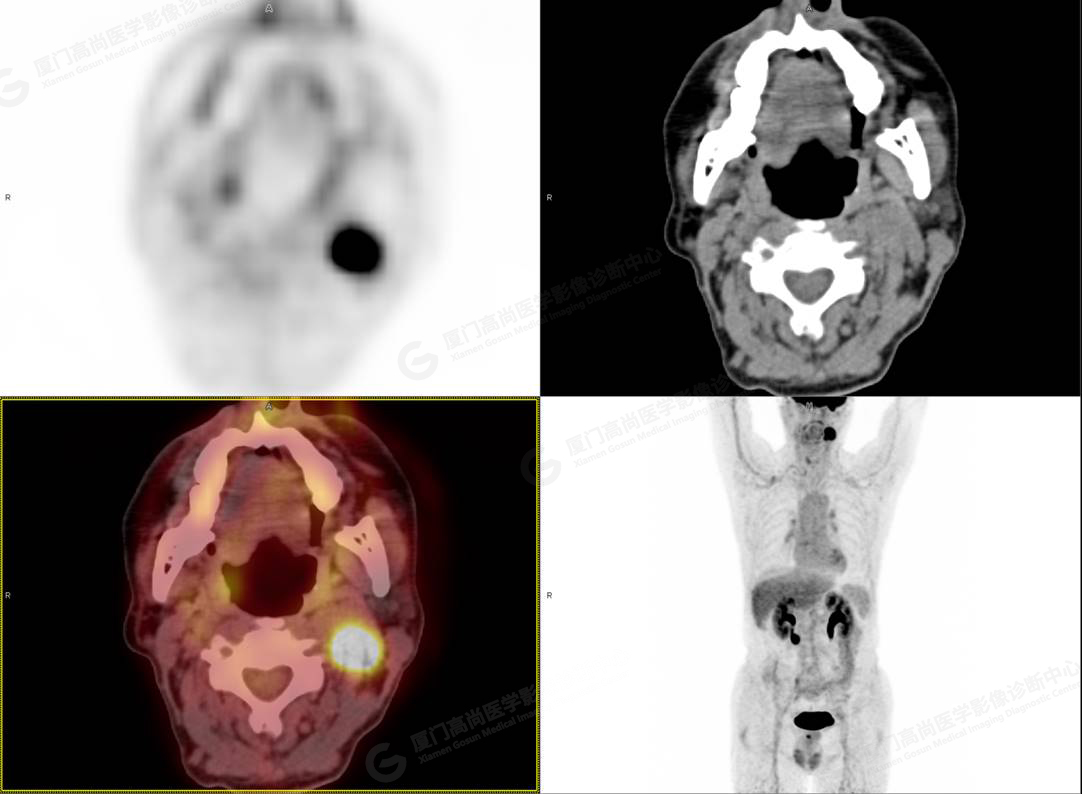

圖1

PET/CT所見:左側(cè)頸部(II區(qū))見腫大淋巴結(jié),大小約2.5cm×2.3cm,其內(nèi)密度不均,邊界尚清,放射性攝取異常增高,早期SUVmax 11.5,延時SUVmax 14.5。

影像診斷: 左側(cè)頸部(II區(qū))腫大淋巴結(jié),代謝異常增高,考慮腫瘤性病變可能性大(淋巴瘤?轉(zhuǎn)移瘤?),建議病理學(xué)檢查明確。